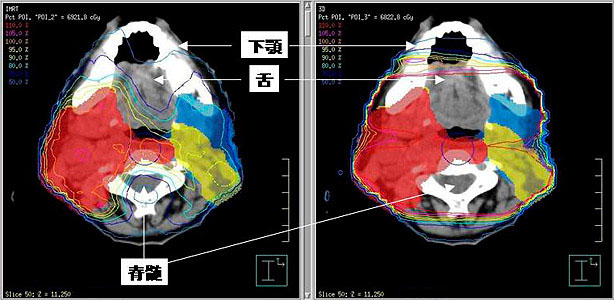

Ct検査よりがん組織と正常組織の区別が明確でct検査とは異なる情報からがんの深さや広がりリンパ節への転移の有無を調べます 7超音波エコー検査 首の表面から超音波をあ てそのはね返りをモニターで見ながら確認. 下咽頭癌の進展範囲を読影する際のチェックポイント 腫瘍の最大径 喉頭への進展の有無 軟骨浸潤の有無 上下方向への進展範囲の決定中咽頭頸部食道 軟部組織浸潤の有無特に梨状癌 梨状窩尖部への進展の有無.

放射線治療 頭頸部がん 九州大学病院のがん診療 九州大学病院 がん

がん診療 放射線治療科 横浜市立大学附属 市民総合医療センター